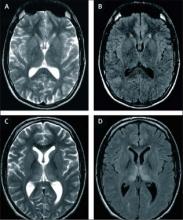

He added that sporadic CJD cases are being identified much earlier now with brain MRI, which has increasingly been used and has become very useful in making and expediting the diagnosis. Unique to vCJD is the "hockey stick" sign on brain MRI, which is a symmetrical hyperintensity in the pulvinar (posterior) nucleiof the thalamus.